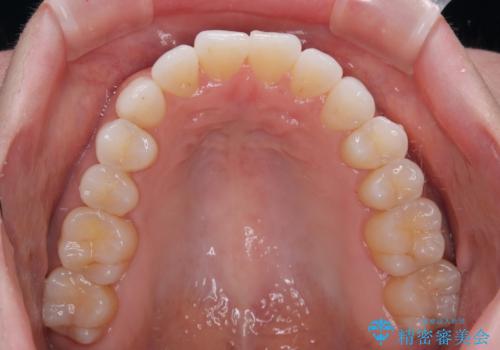

前歯のデコボコをインビザラインで綺麗に

- 上下前歯の叢生を気にして来院された患者様です。

インビザラインでの治療を希望されていて、デコボコの程度が中等度であり、安価なパッケージにて対応可能と判断されたため、インビザライン・モデレートを用いて矯正治療を行うこととしました。

インビザライン・モデレートは、製作できるアライナーの枚数に制限があるため、移動可能な量に限りがあるものの、インビザライン・ライトよりも枚数が多いため、幅広い症例に対応可能です。